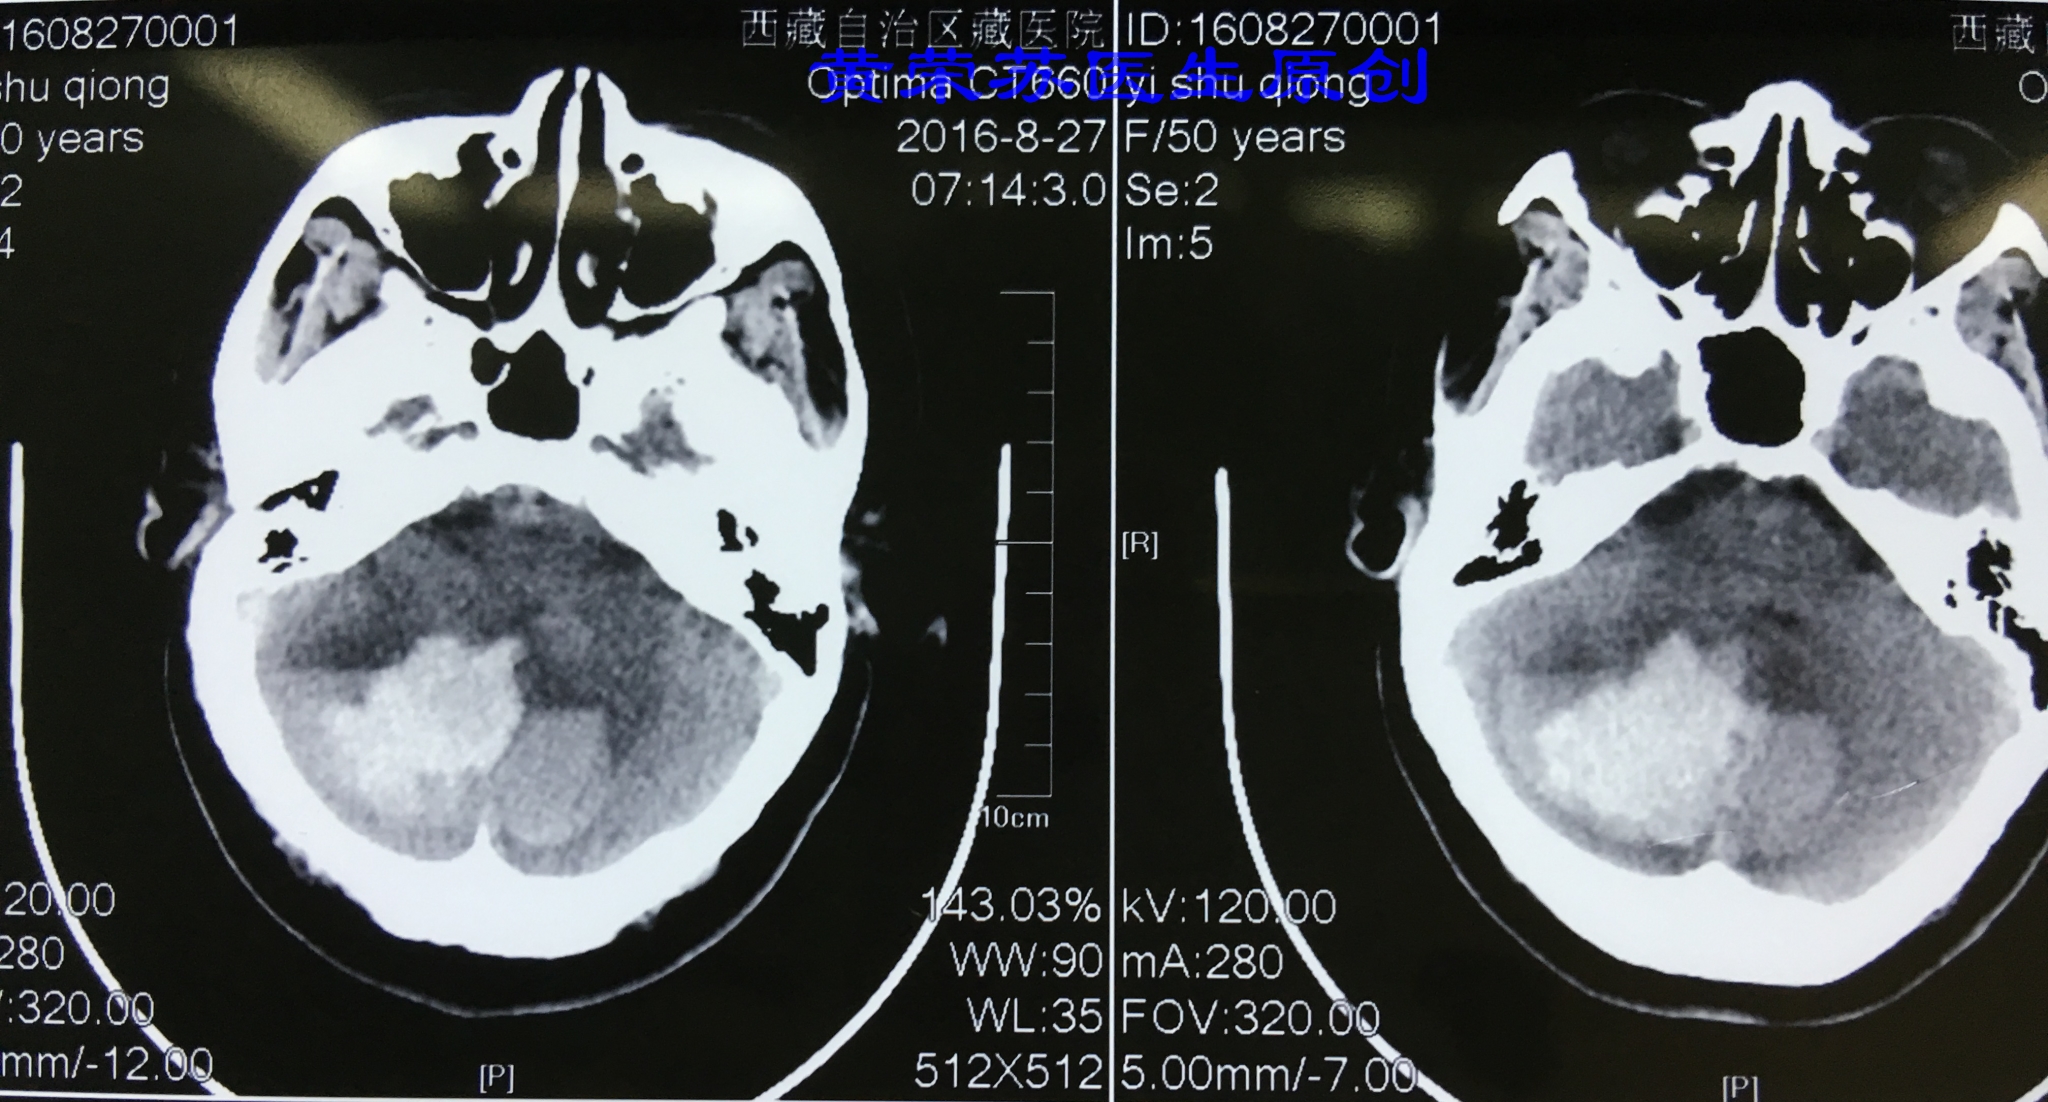

3、小脑出血:高血压脑出血又一常见部位,出血进展快,容易形成脑疝,死亡率高。多数表现为突发眩晕、频繁呕吐,枕部疼痛,一侧上下肢共济失调,眼球震颤,一侧周围性面瘫等。最常见于小脑齿状核动脉破裂所致。

图四、小脑脑出血